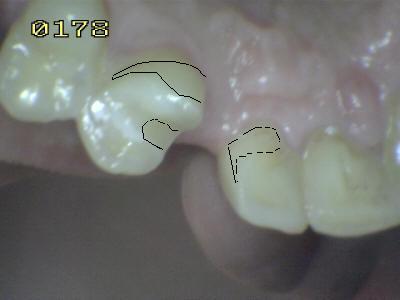

Diseño con lápiz en el

modelo